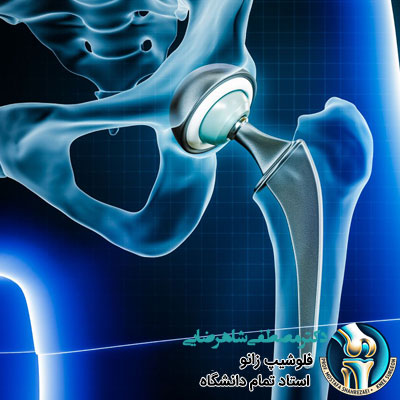

پروتز لگن یک وسیله پزشکی است که جایگزین مفصل لگن آسیب دیده می شود و به افراد کمک می کند تا درد لگن کاهش پیدا کند و راحت تر راه بروند یا فعالیت های روزمره شان را انجام دهند. این پروتزها معمولا برای افرادی استفاده می شوند که به دلیل آرتروز، شکستگی یا آسیب های دیگر مفصل لگن، مشکلات زیادی دارند و حرکت برایشان سخت شده است. یکی از سوالات رایج بیماران، در ارتباط با عمر پروتز لگن است که در ادامه بررسی می کنیم.

انواع پروتز لگن و میزان دوام هر کدام

پروتز لگن انواع مختلفی دارد و هر نوع ویژگی ها و میزان دوام متفاوتی دارد. در ادامه انواع پروتز لگن و میزان دوام تقریبی هر کدام را بررسی می کنیم: